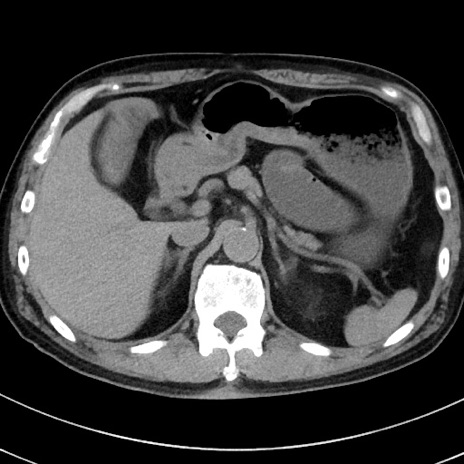

症例38(横断像)

【症例】70歳代 男性

【主訴】腹痛・嘔吐

【現病歴】昨晩より、嘔吐・腹痛あり。今朝になっても嘔吐あり。来院。

【既往歴】心臓バイパス手術、開腹胆摘、腸閉塞

【身体所見】BP 107/71mmHg、HR 116/min、腹部:平坦、軟、下腹部に軽度圧痛あり。反跳痛なし。

【データ】WBC 15100、CRP 0.32